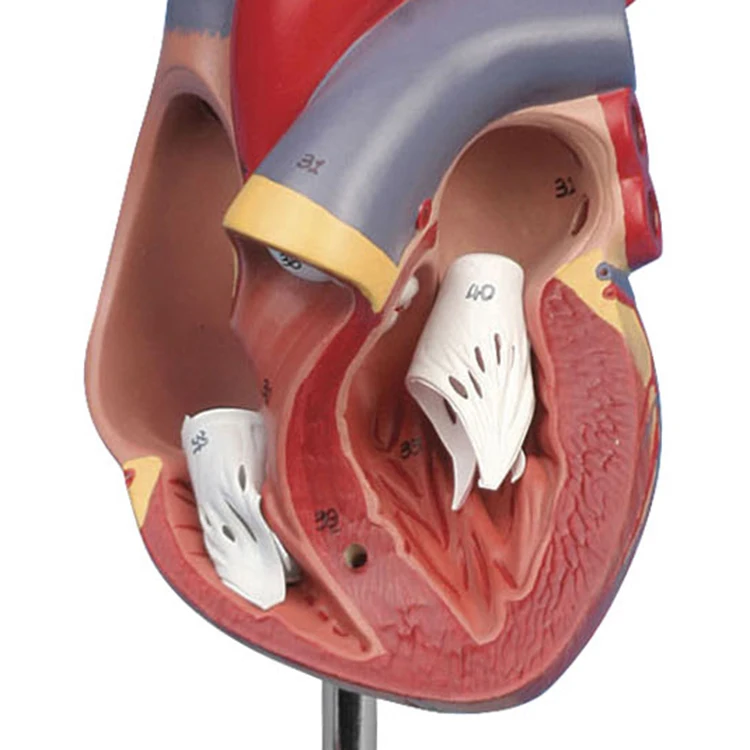

Valentine’s Day ช็อกโกแลตหัวใจ 12 ชิ้น – ของขวัญรังนกแท้ คอซซี่ โมเดลหัวใจมนุษย์ (Human Heart) | Shopee Thailand

โมเดลหัวใจมนุษย์ (Human Heart) | Shopee Thailand หัวใจมนุษย์ ภาพสต็อก – ดาวน์โหลดรูปภาพตอนนี้ – หัวใจ – อวัยวะภายใน …

ขยายกายวิภาคหัวใจมนุษย์รุ่น 3 ชิ้นส่วน – Buy กายวิภาคหัวใจ,หัวใจ … หัวใจมนุษย์ การออกแบบรายละเอียด ภาพประกอบสต็อก – ดาวน์โหลดรูปภาพตอนนี้ …

ชีวิตพลาสติกกายวิภาคหัวใจมนุษย์รุ่น2ชิ้นส่วน – Buy การสอนรุ่น,Anatomy … ช็อคโกแลตรูปหัวใจ [ภาพวาดฟรี] | OkusanPix

หัวใจวิทยาศาสตร์เรื่องกายวิภาคศาสตร์ทางการแพทย์หัวใจมนุษย์รุ่นขาย – Buy … รูปเวกเตอร์ฟรีหัวใจการ์ตูนปุ่ม PNG , หัวใจมนุษย์, หัวใจ, เซลล์ภาพ PNG …

รักสุดใจ! ช่อช็อกโกแลตให้เธอ รวมไอเดียช่อช็อกโกแลตสื่อรัก มอบให้แฟน แบบจำลองหัวใจมนุษย์ขนาดชีวิตที่มีสีพื้นโปร่งใสโรคหัวใจทางการแพทย์แบบ …

แบบจำลองหัวใจมนุษย์ขนาดชีวิตที่มีสีพื้นโปร่งใสโรคหัวใจทางการแพทย์แบบ … Chocolate Heart, Hand-drawn sketch Chocolate s, brown, food png | PNGEgg

Chocolate Heart, Hand-drawn sketch Chocolate s, brown, food png | PNGEgg แบบจำลองหัวใจมนุษย์ขนาดชีวิตที่มีสีพื้นโปร่งใสโรคหัวใจทางการแพทย์แบบ …

แบบจำลองหัวใจมนุษย์ขนาดชีวิตที่มีสีพื้นโปร่งใสโรคหัวใจทางการแพทย์แบบ … ช็อกโกแลต รูปฟุตบอล เหรียญทอง หัวใจ บรรจุ 60 ชิ้น | Shopee Thailand

In-306 3d กายวิภาคศาสตร์หัวใจมนุษย์รูปแบบทางการแพทย์พลาสติกกายวิภาค … หัวใจมนุษย์ ภาพสต็อก – ดาวน์โหลดรูปภาพตอนนี้ – หัวใจ – อวัยวะภายใน, การ …

หัวใจวิทยาศาสตร์เรื่องกายวิภาคศาสตร์ทางการแพทย์หัวใจมนุษย์รุ่นขาย – Buy … หัวใจวิทยาศาสตร์เรื่องกายวิภาคศาสตร์ทางการแพทย์หัวใจมนุษย์รุ่นขาย – Buy …

หัวใจวิทยาศาสตร์เรื่องกายวิภาคศาสตร์ทางการแพทย์หัวใจมนุษย์รุ่นขาย – Buy … Anatomy หัวใจมนุษย์รุ่นพลาสติกทางการแพทย์กายวิภาคหัวใจจัมโบ้รุ่นอวัยวะ …

Anatomy หัวใจมนุษย์รุ่นพลาสติกทางการแพทย์กายวิภาคหัวใจจัมโบ้รุ่นอวัยวะ … รูปช็อกโกแลตหัวใจพร้อมน้ำเชื่อม PNG , วาเลนไทน์วัน, หัวใจ, วันแห่งความ …

3d Anatomy หัวใจมนุษย์รุ่นพลาสติกทางการแพทย์กายวิภาคหัวใจจัมโบ้รุ่น … หัวใจวิทยาศาสตร์เรื่องกายวิภาคศาสตร์ทางการแพทย์หัวใจมนุษย์รุ่นขาย – Buy …

หัวใจวิทยาศาสตร์เรื่องกายวิภาคศาสตร์ทางการแพทย์หัวใจมนุษย์รุ่นขาย – Buy … ส่งไว🚀24ชม. เจบีช็อกโกแลต รูปฟุตบอล เหรียญทอง เหรียญเงิน ทองแท่ง หัวใจ …

ส่งไว🚀24ชม. เจบีช็อกโกแลต รูปฟุตบอล เหรียญทอง เหรียญเงิน ทองแท่ง หัวใจ … Anatomy หัวใจมนุษย์รุ่นพลาสติกทางการแพทย์กายวิภาคหัวใจจัมโบ้รุ่นอวัยวะ …

Anatomy หัวใจมนุษย์รุ่นพลาสติกทางการแพทย์กายวิภาคหัวใจจัมโบ้รุ่นอวัยวะ … ภาพประกอบแบนเวกเตอร์หัวใจมนุษย์ขนาดใหญ่บนพื้นหลังสีขาว ภาพประกอบสต็อก …

หัวใจมนุษย์กายวิภาครุ่นวิทยาศาสตร์การแพทย์รูปแบบการสอน ห้องหัวใจมนุษย์: คำอธิบายโครงสร้างหน้าที่และประเภท

หุ่นจำลองหัวใจมนุษย์ 3d มนุษย์กายวิภาครุ่นหัวใจมนุษย์สำหรับซัพพลายเออร์แบบครบวงจรวิทยาศาสตร์ …

3d มนุษย์กายวิภาครุ่นหัวใจมนุษย์สำหรับซัพพลายเออร์แบบครบวงจรวิทยาศาสตร์ … 3d Anatomy หัวใจมนุษย์รุ่นพลาสติกทางการแพทย์กายวิภาคหัวใจจัมโบ้รุ่น …

3d Anatomy หัวใจมนุษย์รุ่นพลาสติกทางการแพทย์กายวิภาคหัวใจจัมโบ้รุ่น … อวัยวะหัวใจของมนุษย์ | องค์ประกอบกราฟฟิก แบบ PSD ดาวน์โหลดฟรี – Pikbest

หัวใจมนุษย์กายวิภาครุ่นวิทยาศาสตร์การแพทย์รูปแบบการสอน 15 Porch ช็อกโกแลต Fudge แม่พิมพ์ซิลิโคนหัวใจรูปเค้กช็อกโกแลตตกแต่ง DIY …

อุปกรณ์การศึกษากายวิภาคศาสตร์รุ่นหัวใจมนุษย์รุ่นสำหรับโรงเรียนขนาดชีวิต … วิธีทำ “นามะช็อกโกแลต” ของฝากยอดฮิตจากญี่ปุ่น อร่อยหรูดูแพง แต่ทำง่าย …

In-306 3d กายวิภาคศาสตร์หัวใจมนุษย์รูปแบบทางการแพทย์พลาสติกกายวิภาค … บอลลูนหัวใจมนุษย์ Angioplasty เวกเตอร์ ภาพประกอบ ภาพประกอบสต็อก – ดาวน์ …

โรงงานโดยตรงขาย Anatomy หัวใจมนุษย์การฝึกอบรมชุดอวัยวะภายในรุ่น – Buy …